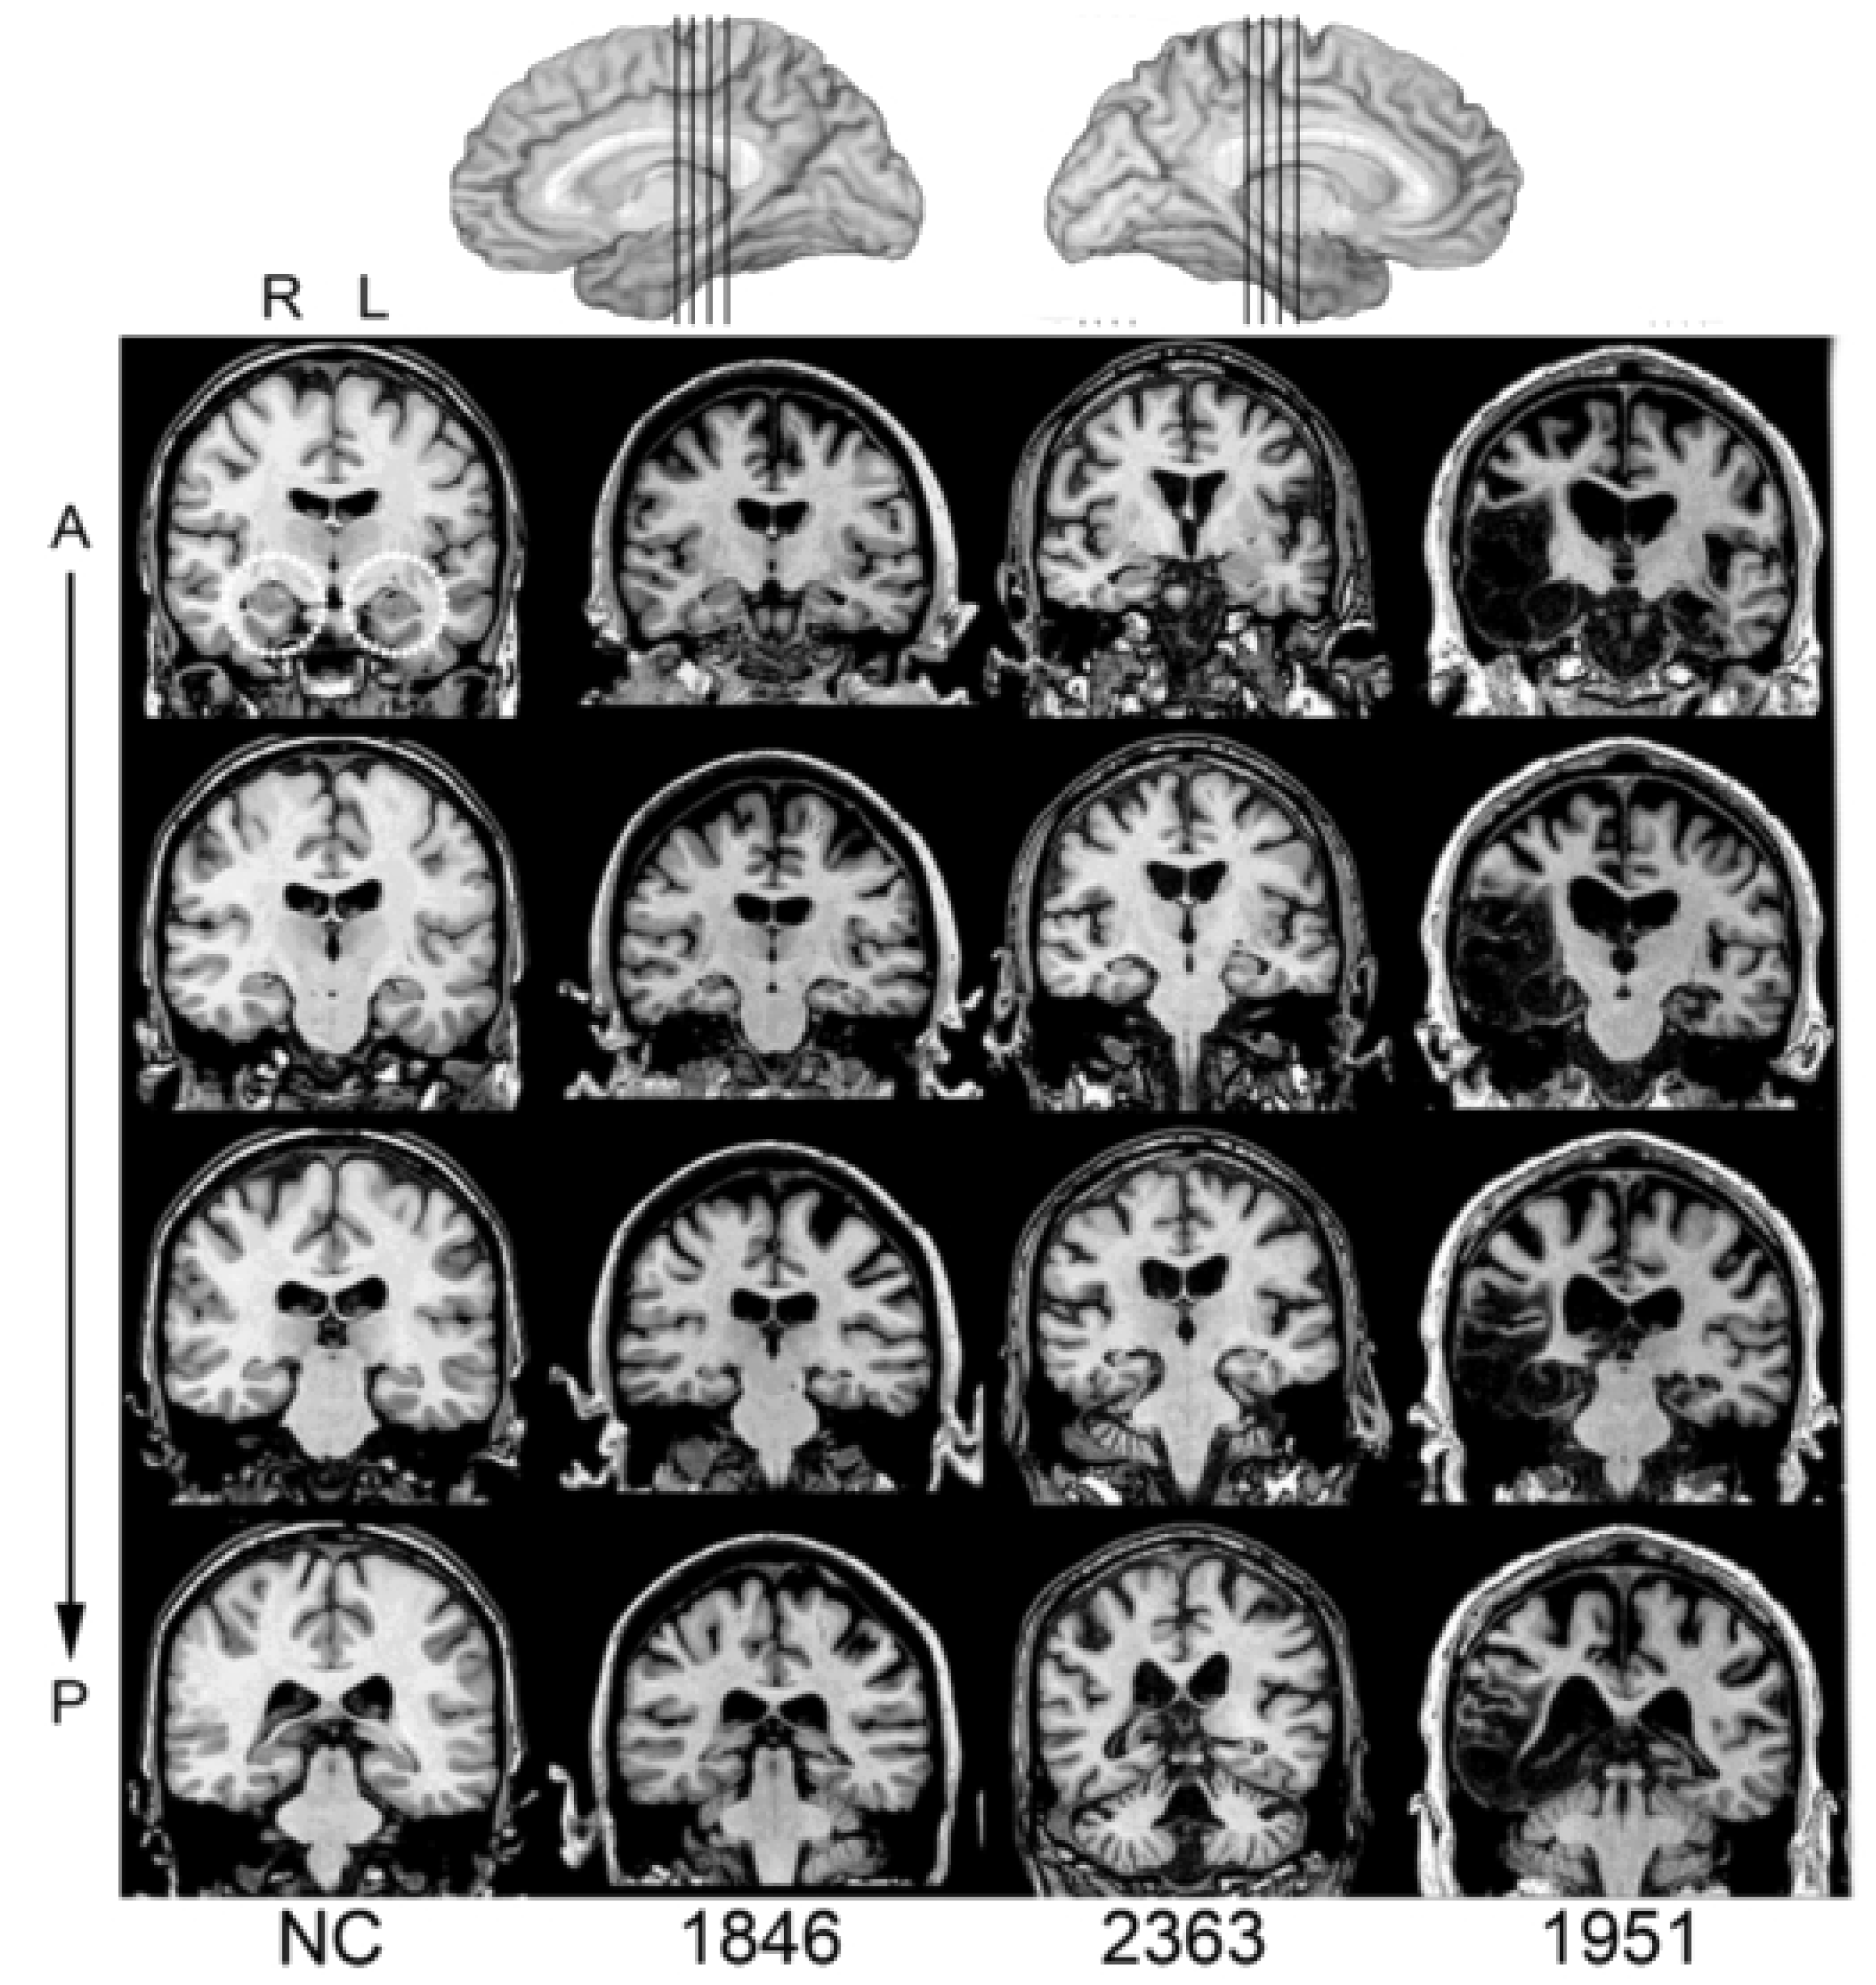

| Participant | Sex | Birth Year | Hand. | Ed. | Etiology | Damage | HC Volume | WAIS-III FSIQ | WMS-III GMI | BNT | TT |

| 1846 | F | 1963 | R | 14 | Anoxia | Bilateral HC | −4.23 | 84 | 57 | 43 | 41 |

| 2363 | M | 1956 | R | 18 | Anoxia | Bilateral HC | −2.64 | 98 | 73 | 58 | 44 |

| 2563 | M | 1955 | L | 16 | Anoxia | Bilateral HC | N/A | 102 | 75 | 52 | 44 |

| 1951 | M | 1952 | R | 16 | HSE | Bilateral HC + MTL | −8.10 | 106 | 57 | 49 | 44 |

| Group Mean | −5.0 | 97.5 | 65.5 | 50.5 | 43.3 | ||||||